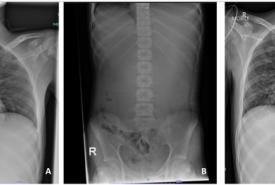

Iatrogenic Tracheal Injury During Hemithyroidectomy: A Case Report

Case Report 29 Jan, 2026